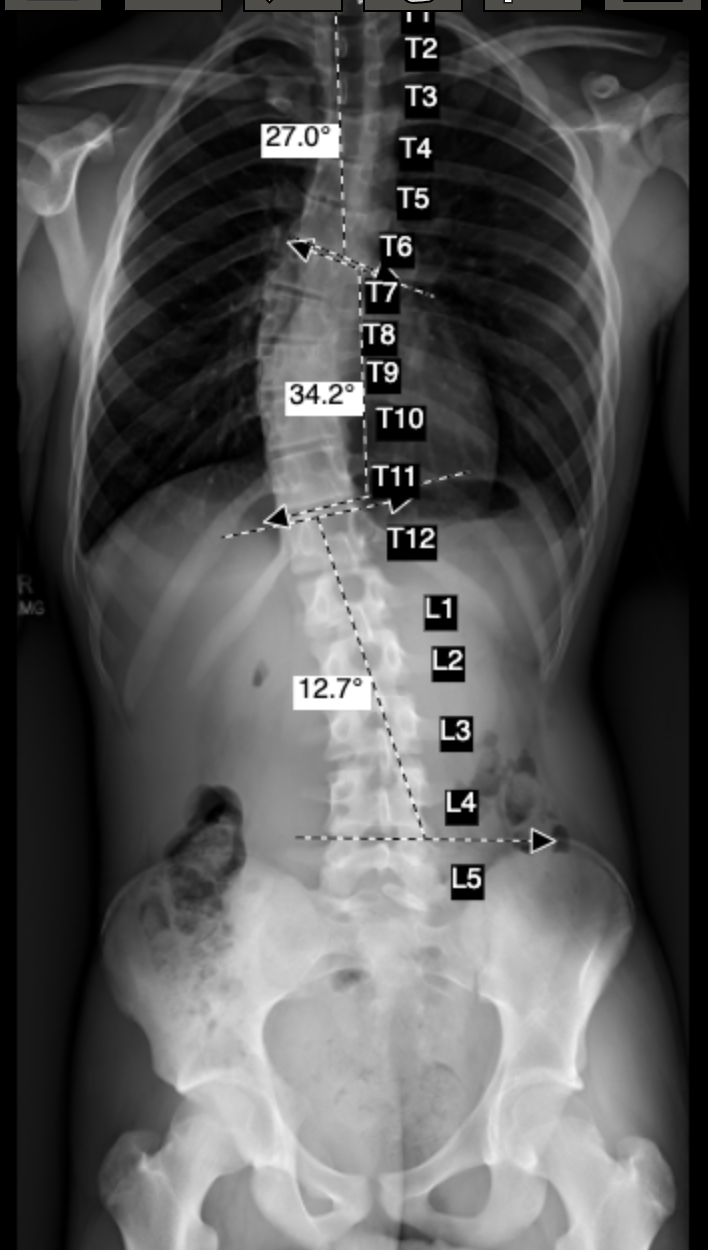

What is Scoliosis?

Any curvature in the spine that measures larger than 10 degrees, that causes the spine to deform in three dimensions. This could be triggered in adolescence (or earlier), as a result of an injury, or from a degenerative condition that presents as we age